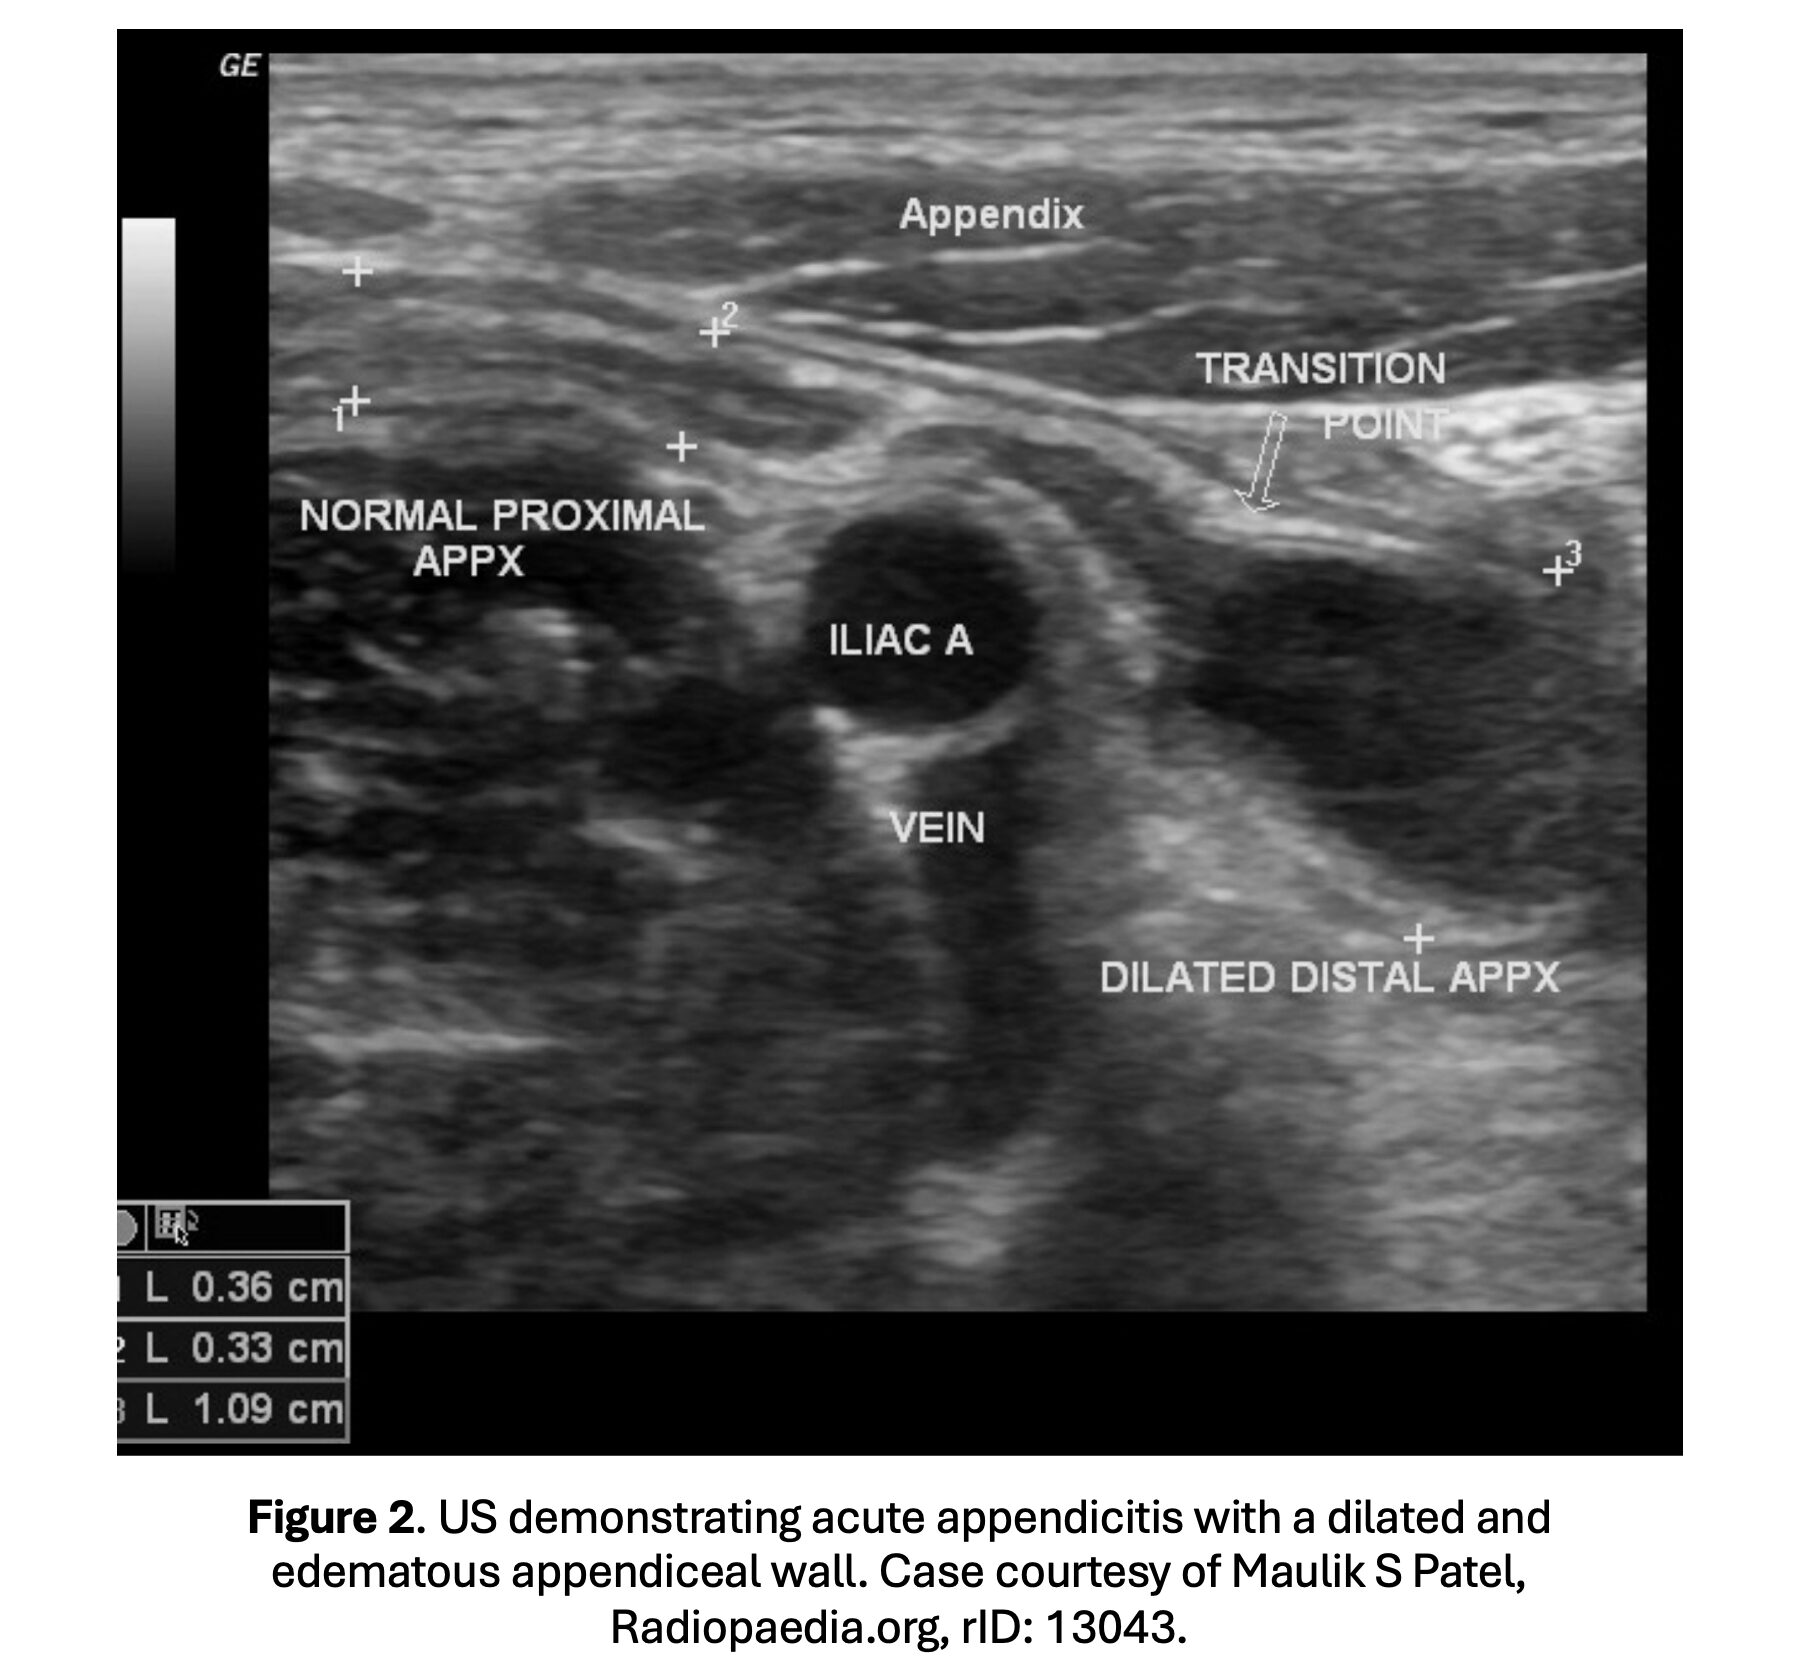

- US findings: noncompressible appendix with wall thickness > 6 mm, pain over the appendix with compression, hyperechoic appendicolith, increased echogenicity of periappendiceal fat, and fluid in the RLQ (Figure 2) (46-57).